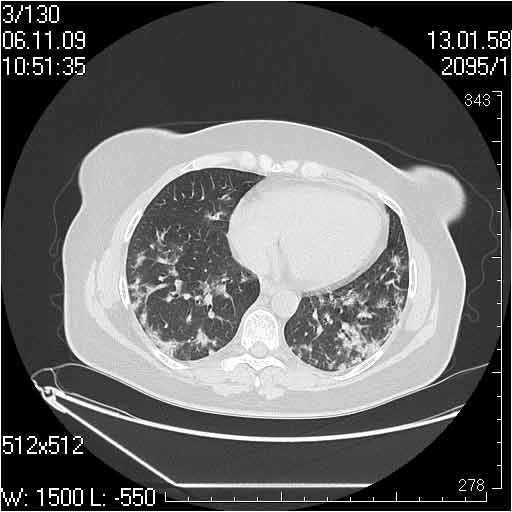

Случай №3

Женщина 51 год

Случай 3:смешанные изменения; подходят для интерстициальной пневмонии, тактика аналогична случаю 1.